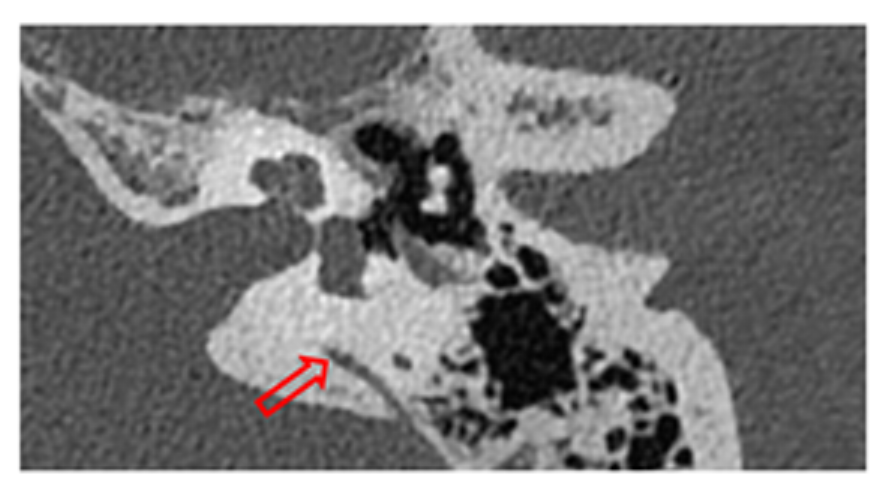

- Imaging studies: Thin-section helical CT scans (SOMATOM CT Scanner Dual Source and Single Source, Siemens Healthineers, Erlangen, Germany) with a slice thickness of 0.4 mm were employed to determine the dehiscences. To avoid selection bias and ensure rigorous criteria, only patients who presented at least one objective auditory fluctuation in pure-tone audiometry and/or those with a minimum of two episodes of spontaneous vertigo lasting longer than 20 min were selected for this test. These symptoms were used as they are considered reliable indicators of potential underlying pathologies that justify the use of advanced imaging techniques [1,8]. If these criteria were met, a 3T MRI (MAGNETOM Skyra, Siemens, Erlangen, Germany) was performed using a T2-FLAIR sequence for four hours after intravenous gadolinium administration to assess the presence of cochlear and vestibular EH.

| Type III Cochleo–facial and Cochleo-ICA | 2 | 2.32% | 103 dB | Yes (n = 1) | Yes (n = 1) | Yes (n = 1) | Gusher during cochlear implant | ||

| Double dehiscences (Cochleo–ICA + Cochleo–facial) and SSCD + jugular vein-EVA | 2 | 2.32% | 59 dB | Yes (n = 1) | Yes (n = 1) | Yes (n = 2) | Gusher during cochlear implant | ||